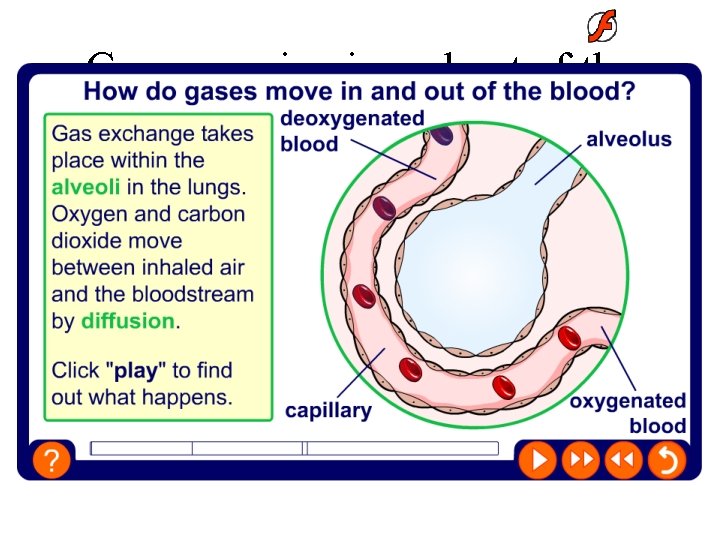

Gases moving in and out of the blood